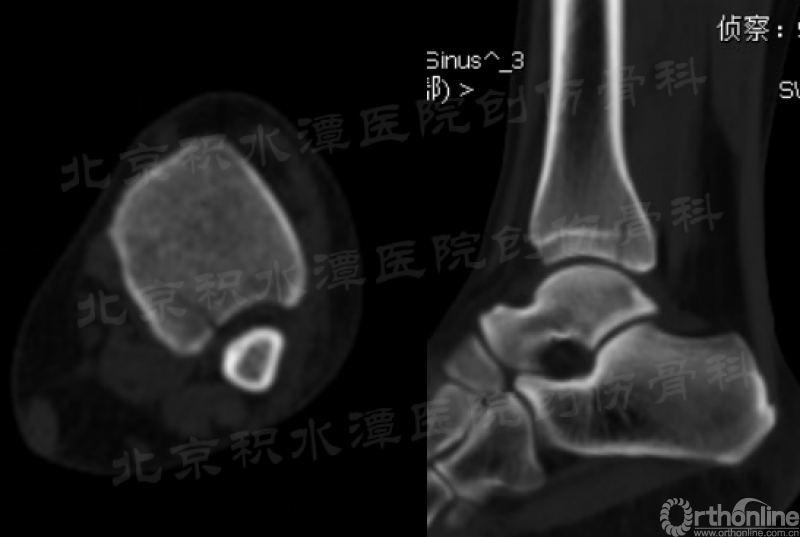

复查CT可见后踝骨折无移位(猜测当时踝关节处于跖屈位,制动电动车使左踝受到轴向应力),胫腓骨正侧位带膝未见腓骨近端骨折。

对于以上这例病例,这种骨折类型也不是常见的踝关节骨折类型,若是没有很仔细的查体和阅片,很容易发生漏诊。